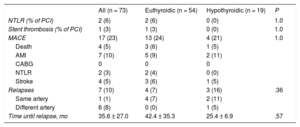

Long-term clinical follow-up was performed in all patients (4.1 ± 3.8 years; median, 3.1 [1.0-6.7] years) with a general MACE rate of 23% (n = 17) (Table 4), mainly due to revascularization and reinfarction. Fibrinolysis, previous anticoagulation, the type of conservative or interventional treatment, and corkscrew arteries were not associated with an increased long-term risk of MACE. No differences were found in the clinical course of patients with SCAD according to thyroid function status (HR = 0.76, 95%CI, 0.23-2.47; P = .65). Seven patients (10%) developed SCAD recurrence during follow-up, generally in a different artery from the first one (all of these patients received beta-blocker treatment). Hypothyroid patients had an SCAD recurrence rate similar to that of euthyroid patients (HR, 0.22, 95%CI, 0.38-1.35; P = .1).

Events During Follow-up in the Spontaneous Coronary Artery Dissection Group

| All (n = 73) | Euthyroidic (n = 54) | Hypothyroidic (n = 19) | P | |

|---|---|---|---|---|

| NTLR (% of PCI) | 2 (6) | 2 (6) | 0 (0) | 1.0 |

| Stent thrombosis (% of PCI) | 1 (3) | 1 (3) | 0 (0) | 1.0 |

| MACE | 17 (23) | 13 (24) | 4 (21) | 1.0 |

| Death | 4 (5) | 3 (6) | 1 (5) | |

| AMI | 7 (10) | 5 (9) | 2 (11) | |

| CABG | 0 | 0 | 0 | |

| NTLR | 2 (3) | 2 (4) | 0 (0) | |

| Stroke | 4 (5) | 3 (6) | 1 (5) | |

| Relapses | 7 (10) | 4 (7) | 3 (16) | .36 |

| Same artery | 1 (1) | 4 (7) | 2 (11) | |

| Different artery | 6 (8) | 0 (0) | 1 (5) | |

| Time until relapse, mo | 35.6 ± 27.0 | 42.4 ± 35.3 | 25.4 ± 6.9 | .57 |

AMI, acute myocardial infarction; CABG, coronary artery bypass grafting; MACE, major adverse cardiovascular events; NTLR, need for target lesion revascularization; PCI, percutaneous coronary intervention.

Unless otherwise indicated, the data represent No. (%) or mean ± standard deviation.